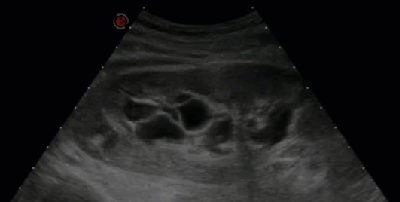

ИИ как спасение: Как нейросети расшифровывают тайны наших почек Здоровье – это самое ценное, что у нас есть. И когда речь заходит о таком важном органе

ИИ в диагностике почек: как нейросети видят то, что упускает глаз врача Приветствую, друзья! Сегодня мы погрузимся в захватывающий мир медицины и искусственного интеллекта.

ИИ на страже здоровья почек: как технологии меняют диагностику кист Привет‚ друзья! Сегодня мы хотим поделиться с вами нашим опытом погружения в

Искусственный Интеллект на Страже Здоровья Почек: Как ИИ Обнаруживает Камни на Снимках Мы живем в эпоху, когда технологии проникают во все сферы нашей